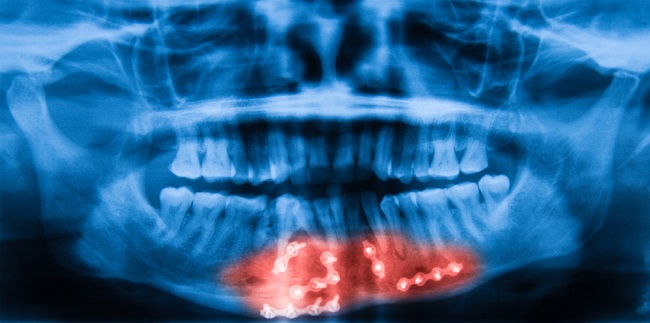

Fraktur mandibula atau patah tulang rahang terjadi sekitar 36−70% dari seluruh jenis fraktur fasial, di mana 60% dari seluruh kasus fraktur mandibula merupakan fraktur multipel. Kondisi yang menyertai fraktur ini umumnya adalah gigi geligi yang tidak selaras, perdarahan gingiva, dan kesulitan membuka rahang.[1]

Closed reduction disertai dengan fiksasi maksila-mandibula merupakan penatalaksanaan fraktur tanpa membuka membran mukosa dan kulit. Sementara itu, open reduction disertai dengan fiksasi internal merupakan terapi bedah dengan membuka membran mukosa dan kulit.[1,2]

Normalnya, penyembuhan membutuhkan waktu 4−6 minggu pada fraktur mandibula yang dilakukan fiksasi intraoral, baik dengan teknik maxillomandibular fixation (MMF) atau rigid internal fixation (RIF). Namun, pasien dengan MMF biasanya akan mengalami penurunan berat badan yang lebih signifikan karena kesulitan makan akibat fiksasi maksila-mandibula, sedangkan pasien dengan RIF memiliki risiko infeksi yang lebih parah.[7-9]